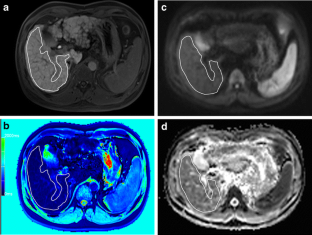

Fig. 1

Fig. 2